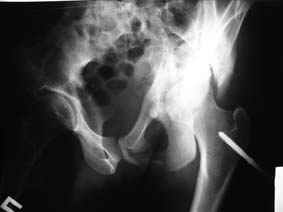

Уважаемые коллеги! Хотелось бы услышать совет по тактике лечения представлленого больного.Поступил после лечения в одном изотделений области. Травма 2,5 месяца назад. После выведенияиз шока был произведен остеосинтез перелома бедра, предплечья, до перевода к нам проводилосьвытяжение по оси шейки бедра за стержень, введенный в большой вертел. На сегодня деформацияригидна, клинически мобильности не определяется. Заранее признателен. P.S. Данный вид травм не включен в перечень "высокотехнологичных операций", направить длялечения по квотам Минздрава очень сложно.

Это обзорные и косые снимки

Привет, Леонид. Оскольчатый высокий двухколонный перелом в такие сроки трогать не надо, т.к. это про такие переломы сказано: "кто с ножом на Ж. пойдет тот в ней и останется...".